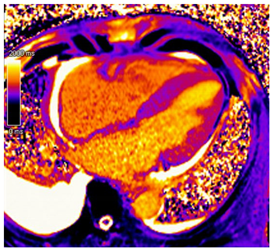

| T1 time | Elevated native T1 time | ![]() |

| T2 Time | Possibly elevated T2 time but not as high as reported in myocarditis or myocardial infarction | ![]() |